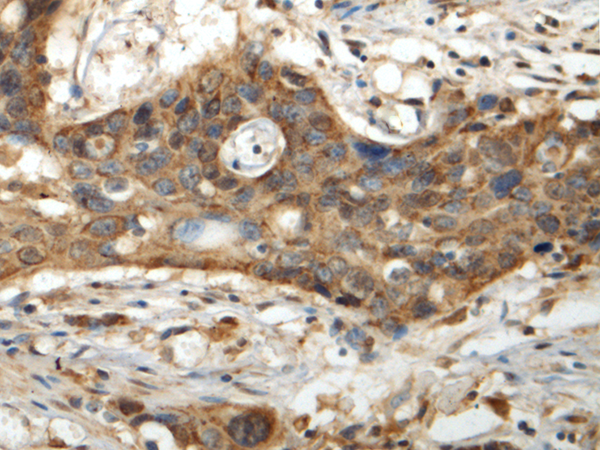

IHC positive control: |

Human esophagus cancer |

IHC Recommend dilution: |

150-300 |